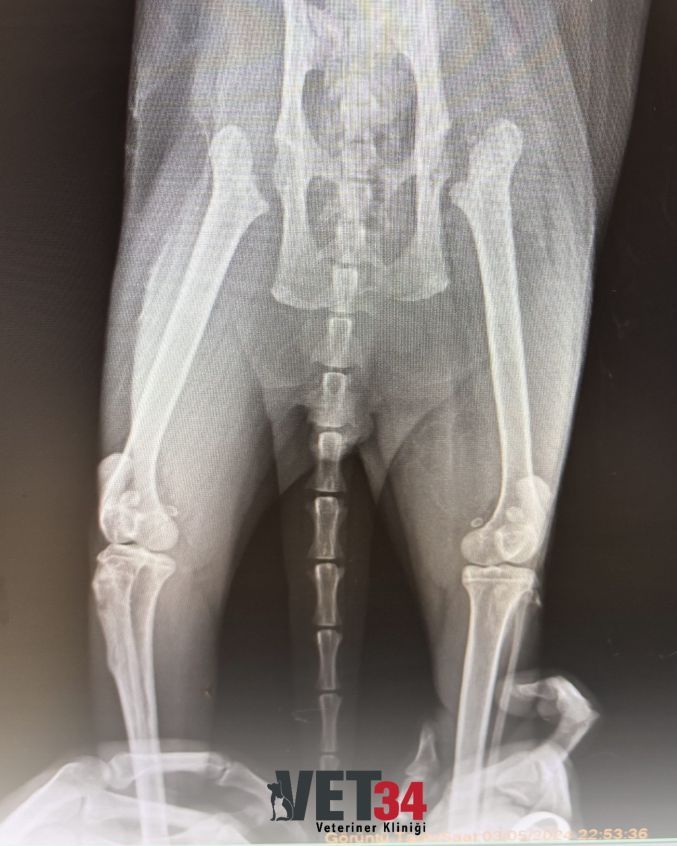

Aslan ile tanışmamız 26 Nisan 2023 tarihinde gerçekleşti. İlk muayene ve değerlendirmelerde ortopedik bir problem tespit edildi ve gerekli cerrahi müdahale planlandı. Süreç başarıyla tamamlandıktan sonra Aslan için düzenli bir takip programı oluşturuldu.